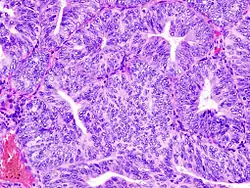

.jpg)

El tratamiento primario es quirúrgico, que consiste en, al menos un muestreo citológico del fluido peritoneal, exploración abdominal, palpación y biopsia de algún nódulo linfático, histerectomía abdominal y remoción de ambos ovarios y trompas de Falopio (denominado salpingooforectomía).[1] La linfadenectomía o el remover los nódulos linfáticos pélvicos y para-aórticos, se realiza a veces para tumores que tiene características de alto riesgo, tales como un tumor patológico seroso o de células claras grado III, la invasión de más de la mitad del miometrio o la extensión hacia la cérvix o anexos. A menudo, puede ser indicado el remover el omento.

Se prefiere la histerectomía abdominal por encima de la vaginal, porque permite al examinador evaluar y obtener lavados de la cavidad abdominal y detectar así mayor evidencia del cáncer.